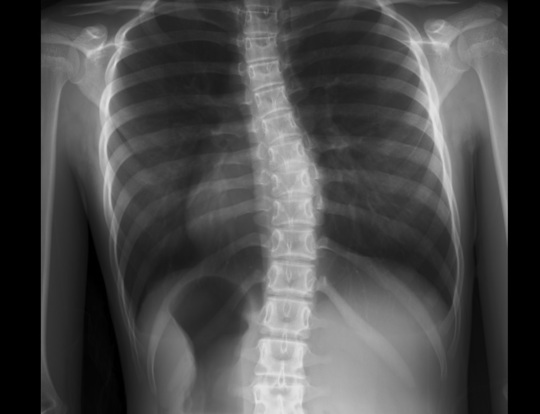

コブ角の計測・カーブパターンの評価

コブ角の計測方法

お持ちいただいたレントゲン画像からcobb角を計測します。

cobb角とは一般的に側弯症の進行を評価する角度になります。